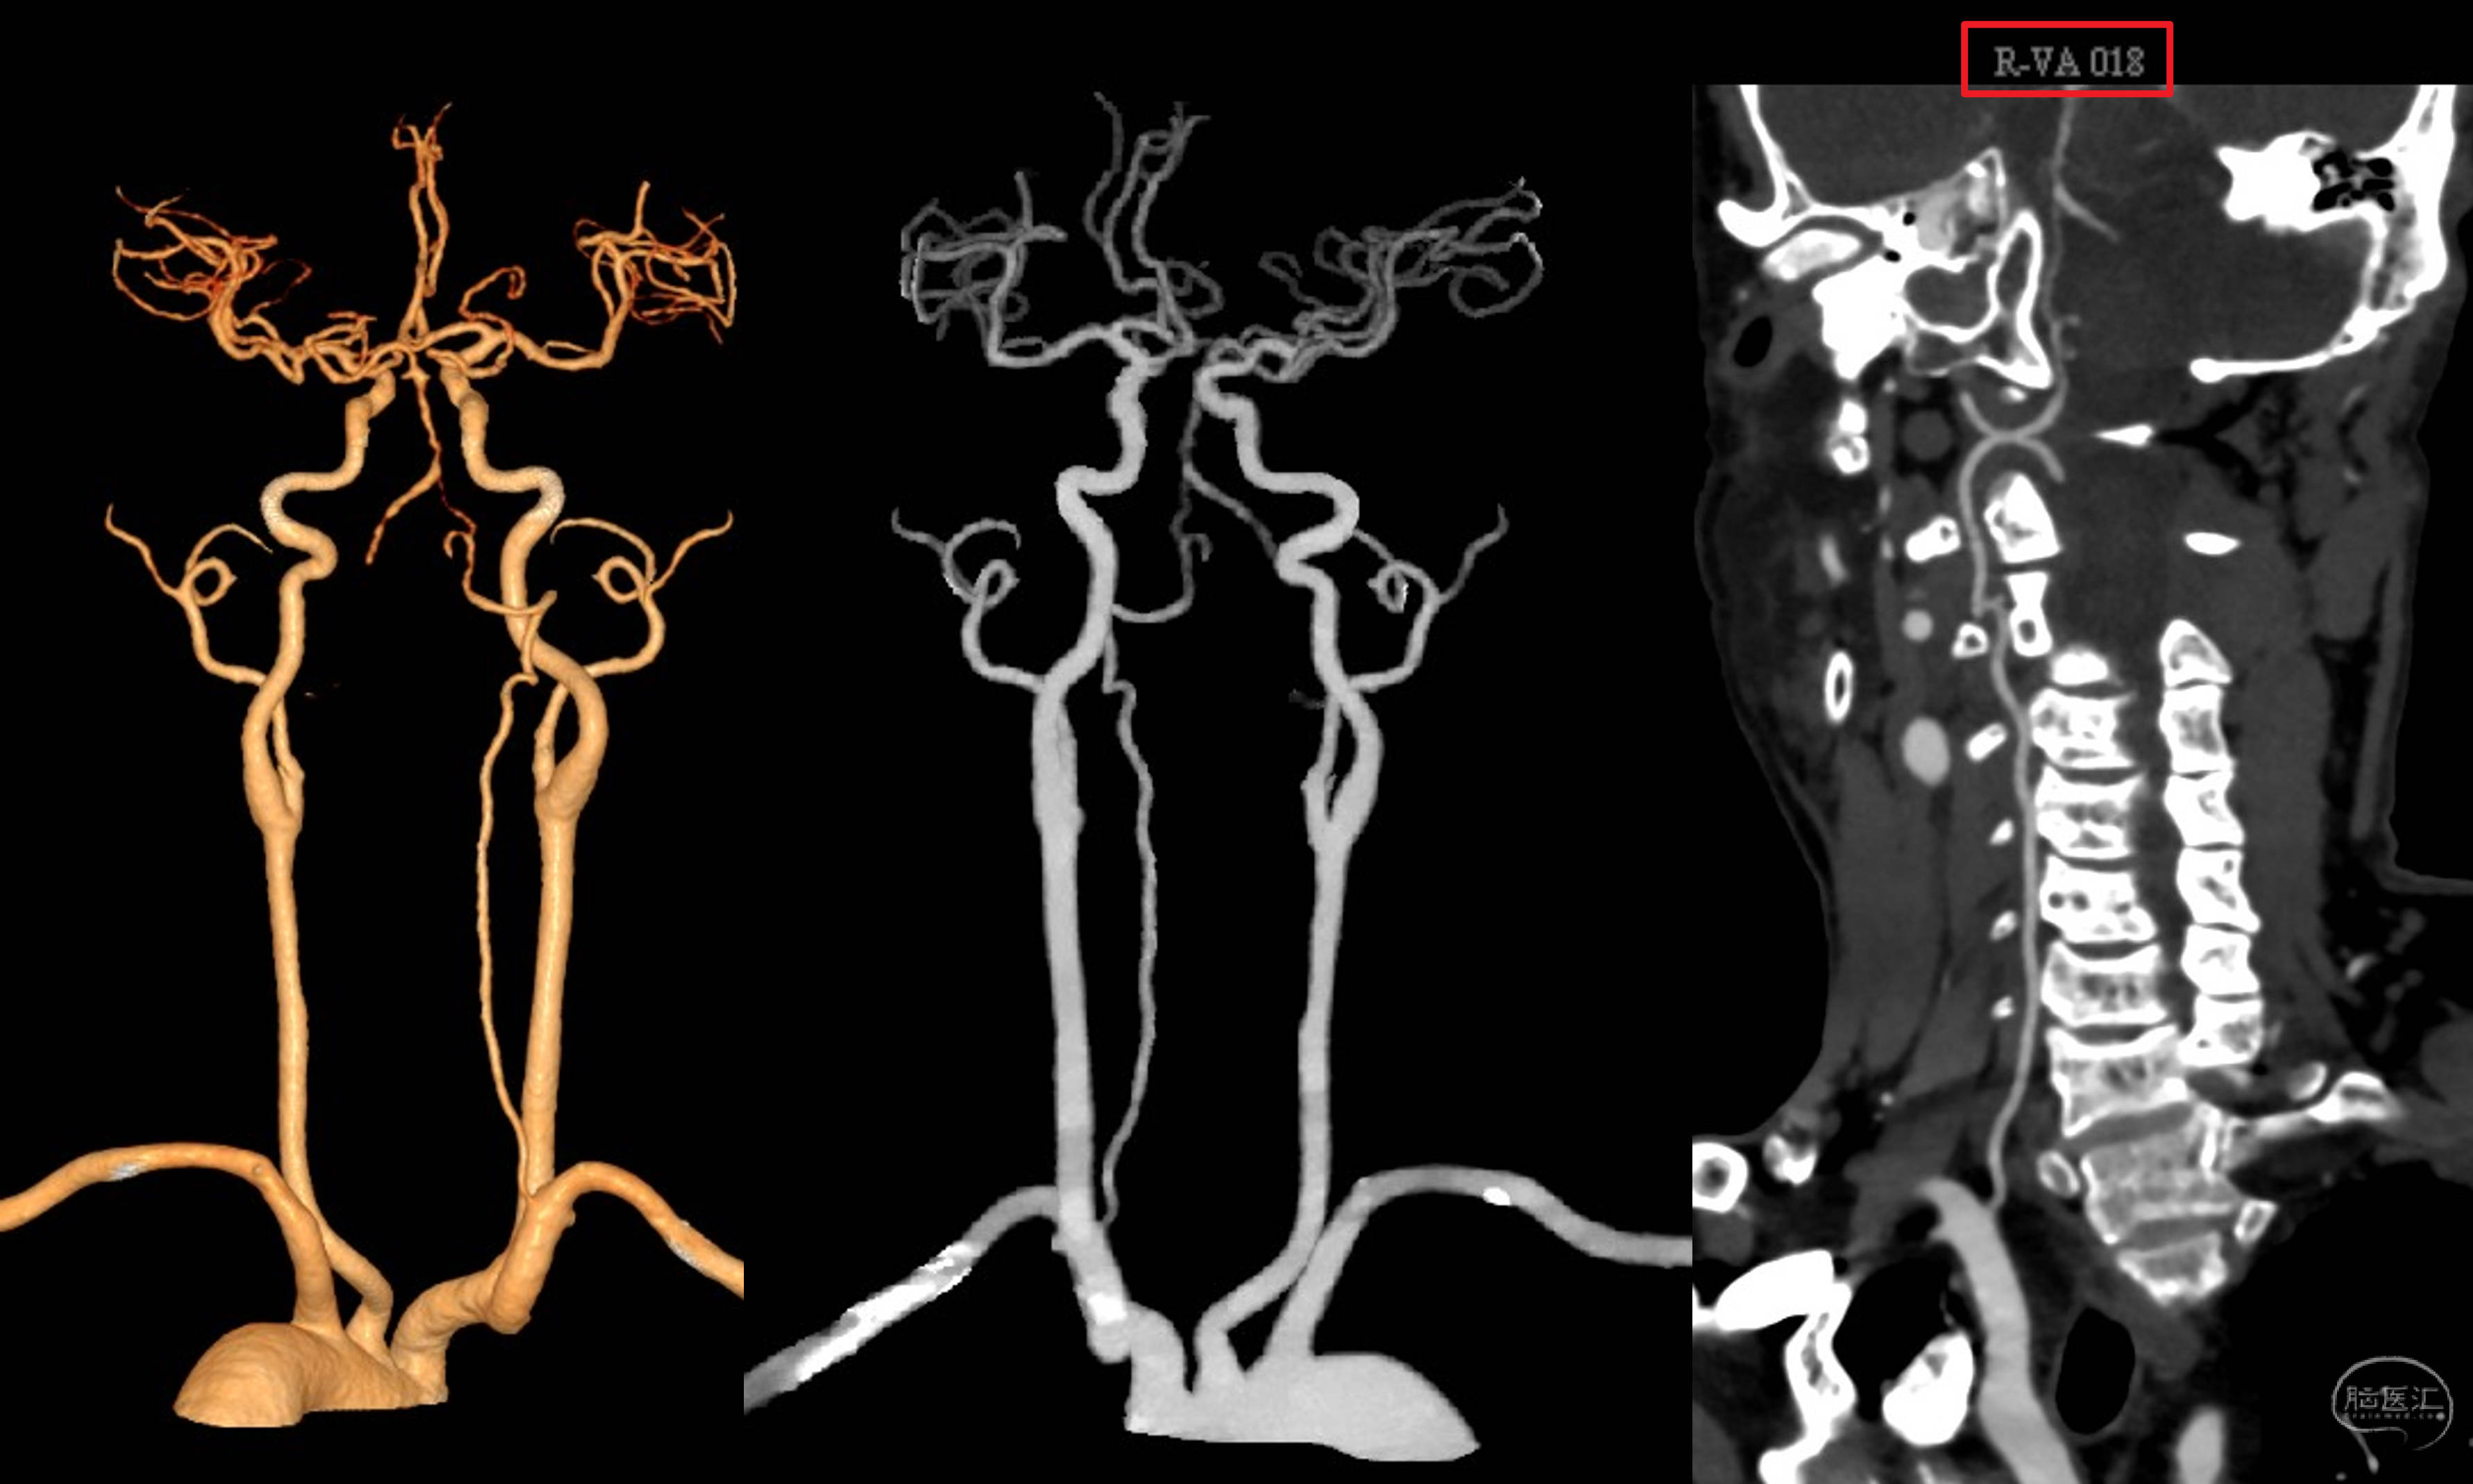

入院后的CTA确认闭塞,右侧VA发育不良!

三维重建,提示骨性结构完好,OA-V3桥血管通畅,吻合口无狭窄。超声提示血流量33ml/min。